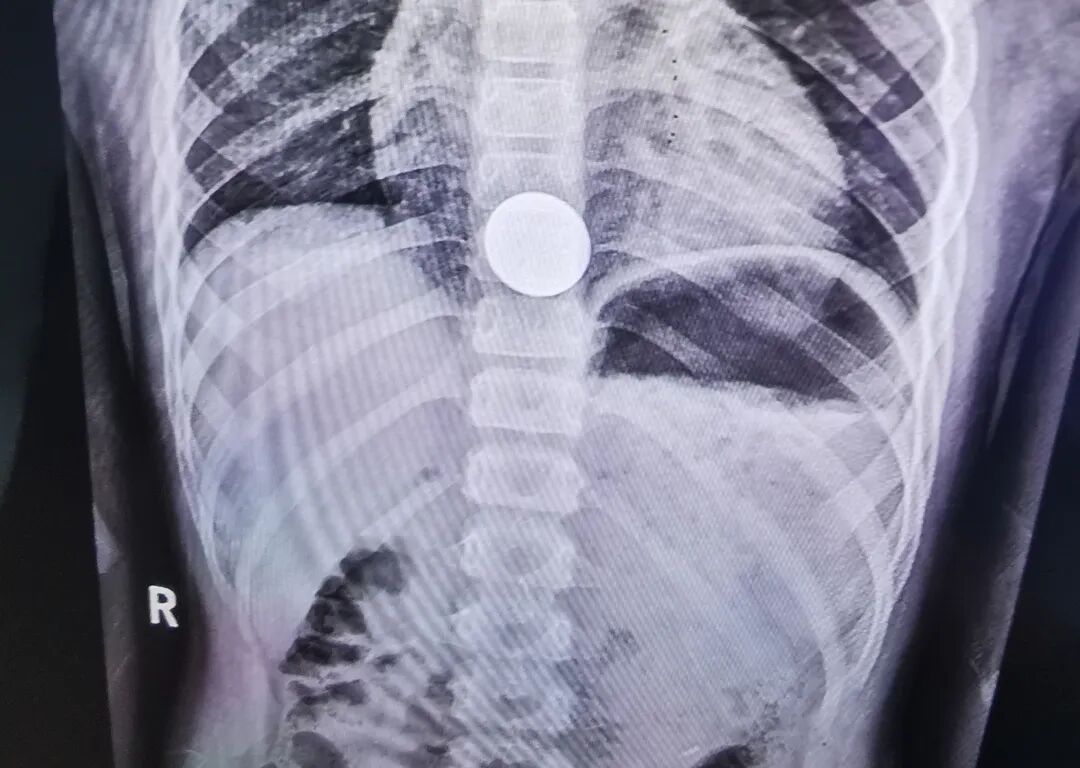

5月29日下午5点半,一对家长抱着孩子急匆匆奔入新泰市中医医院综合楼三楼小儿外科门诊,小儿外科坐诊专家询问得知患者来自新泰羊流,该五岁孩子在玩硬币时,不小心把一枚1元硬币从嘴里吞下,在当地卫生院拍胸片后建议到上级医院诊疗。

当妈妈抱着小患者出现在李迎吉主任的面前时,孩子用手捂着自己的胸口下方,一直喊着:“妈妈,疼!妈妈,疼!……”看过孩子妈妈手机里拍存的胸部片子,发现硬币卡在食管下段、膈肌上水平。李迎吉介绍,因为孩子年龄小,贲门狭窄,硬币卡在食管下端下不去,在此部位较危急,食管痉挛导致孩子异常疼痛,时间长了还会引起出血、溃疡甚至穿孔。